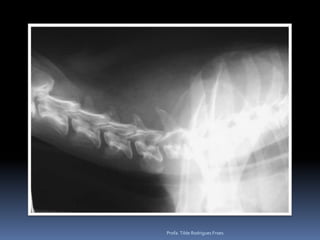

Exame radiográfico Esqueleto apendicular e axial“Achados radiográficos”Doença articular degenerativaEscápulo umeral (Achado radiográfico)Correlacionado a Displasia coxofemoral (relevância clínica)Espondiloses - COLUNA*Instabilidade lombosacral*Espondilomielopatia cervical*Doença do disco IV*DiscoespondiliteOsteoartrose do JoelhoProfa. Tilde Rodrigues Froes

Exame radiográfico Esqueletoapendicular e axial“Achados radiográficos”Doença articular degenerativaEscápulo umeral (Achado radiográfico)Correlacionado a Displasia coxofemoral (relevância clínica)Espondiloses - COLUNA*Instabilidade lombosacral*Espondilomielopatia cervical*Doença do disco IV*DiscoespondiliteOsteoartrose do JoelhoProfa. Tilde Rodrigues Froes